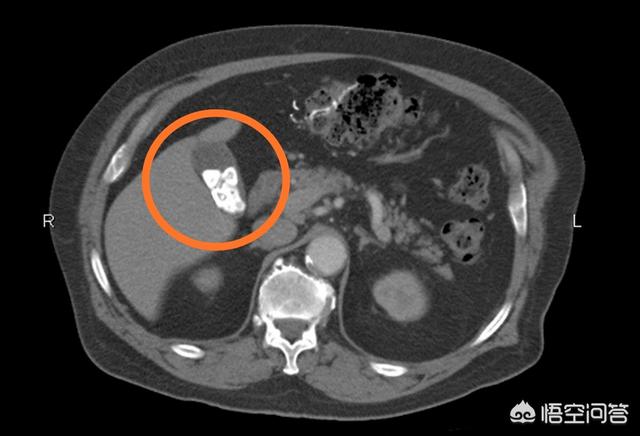

上图是一位胆囊结石患者的腹部CT图像,可以看到胆囊内(画圈)多发大小不等的高密度结石影。